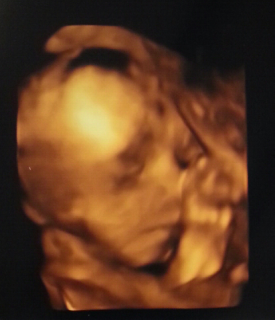

写真:24w2d:びびさん

2Dエコー、顔のアップです。

目を開けているように見えてちょっと怖いですが、4Dだと鼻が高くて目が大きくて旦那の遺伝子をもろに受け継いでます。

先生には、かなりいい顔してますよ!って言われました。

イタリアx日本の混血で推定872gの男の子です。先月に引き続き逆子!次の検診までひっくり返っていて欲しいです。お腹も突き出てきて、胎動の頻度が増えました!最近は眠気が物凄いです。